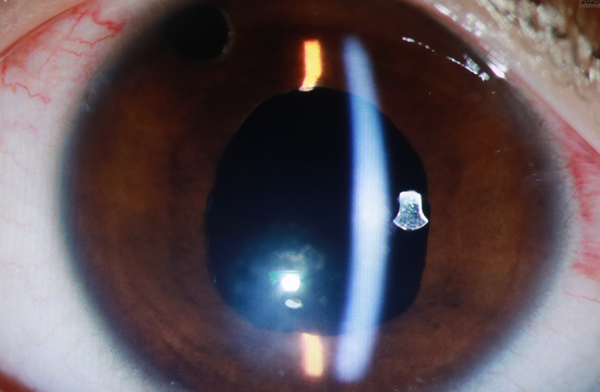

而整个手术中最具战略意义的一步,也是难度比较大的一步,将一枚米粒大小的氟轻松缓释剂固定,以更好发挥药效。

“不要小看这个‘小棒棒’,对于这种顽固性葡萄膜炎患者,控制炎症是手术成功和维持长期治疗的重点因素。”李玉军表示,

“它能在长达2-3年的时间内,以恒定速率释放低剂量的抗炎药物,抑制眼内炎症,为视功能的恢复争取宝贵时间。”